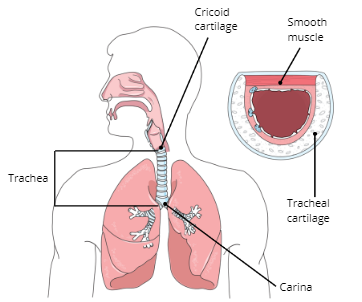

Cricoid Cartilage

Trachea

Carina

Function of Trachea